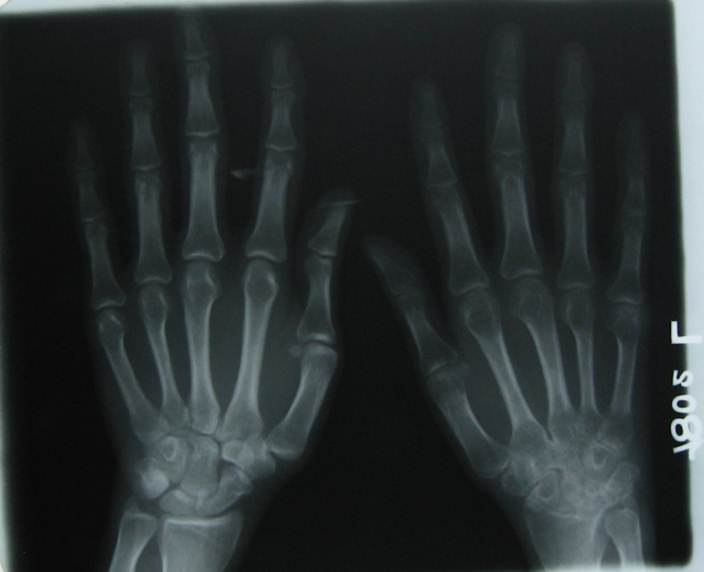

RHEUMATOID ARTHRITIS1